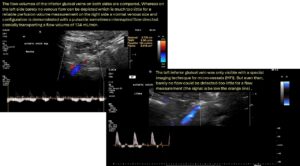

The PixelFlux measurement clearly demonstrates the insufficiency of the collateral pathways of the left renal vein while the patient is lying fasting. The perfusion of the left kidney is then only 76% of that of the right kidney.

While lying postprandially, severe suppression of perfusion in both kidneys is evident, with the left kidney receiving only 20% of the severely reduced blood flow of the right kidney. Sitting while fasting impedes blood flow to the right kidney. Such precise statements about haemodynamic effects and blood flow distribution volumes can only be made using the PixelFlux technique.

The clinically suspected and intraoperatively confirmed tronc réno-rachidièn could not initially be visualised sonographically, as the high congestive pressure of the spinal canal meant that there was no effective blood flow that would have produced a Doppler signal. This was an expression of the enormous intraspinal pressure, which corresponded to the pressure in the compressed left renal vein.